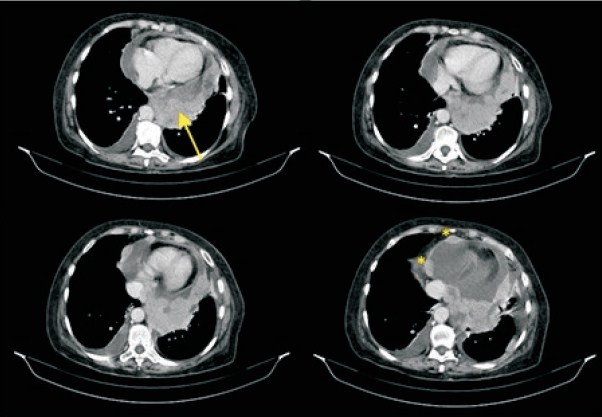

Se realizó tomografía computarizada de tórax que confirmó la presencia de una gran masa sólida y heterogénea a nivel de la parte central del pericardio posterior de 67 por 82 por 54 mm, con signos de compresión de la aurícula izquierda y de las venas pulmonares, así como múltiples masas nodulares localizadas a nivel del pericardio parietal (figura 2).

Figura 2: Tomografía computarizada de tórax. Se constata gran masa pericárdica heterogénea y sólida a nivel posterior (flecha) y múltiples masas nodulares localizadas en el pericardio(*).